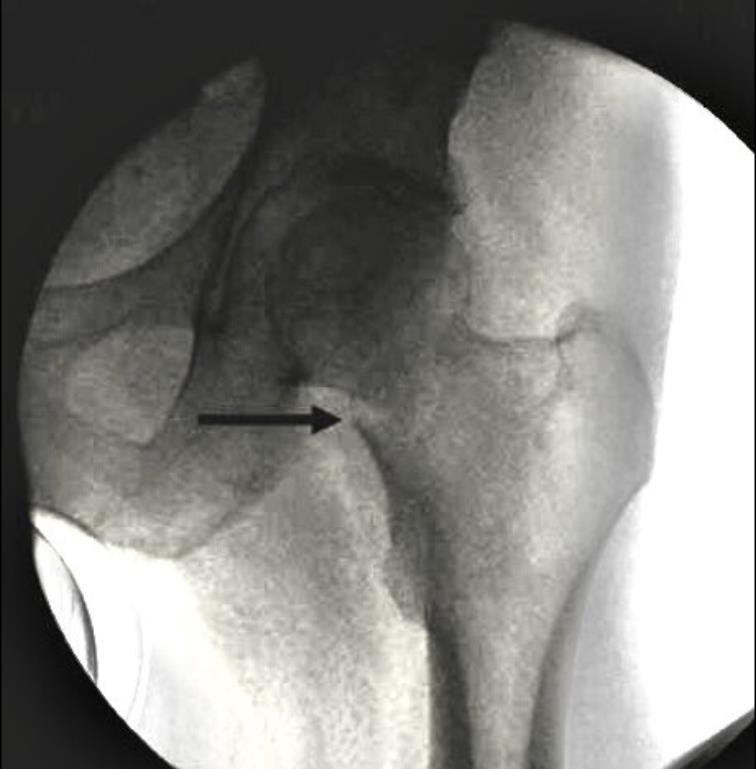

阳性支撑与阴性支撑

1、阳性支撑是指股骨颈骨折的远骨折端突向近侧骨折断端内下缘的内侧。

图3 阳性支撑更稳定

2、阴性支撑是指近侧骨折断端(股骨颈、头)的内下缘突向股骨颈远骨折端内上缘的内侧。阴性支撑容易导致复位的股骨头移位,继而发生内翻,内固定失败率高。

图4 阴性支撑不稳定